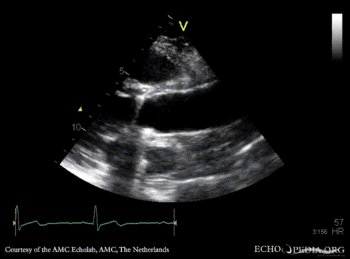

Bentall and aortic valve prosthesis

Courtesy of: AMC Echolab, AMC, The Netherlands

PLAX: aortic valve prosthesis and Bentall in situ PLAX with Color Doppler